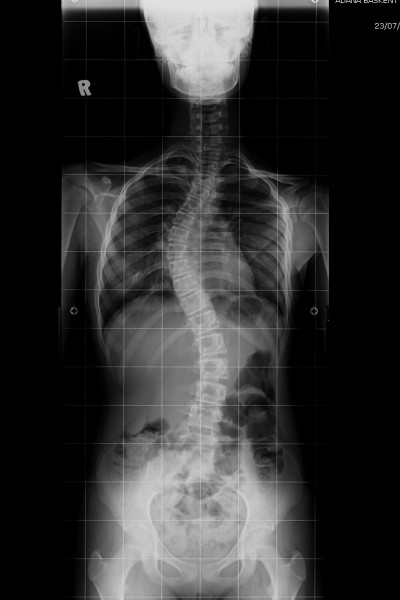

Gövdeye yandan bakıldığı zaman omurgada normal olan eğrilikler görülür. Sırt bölgesinde dış bükey bir eğrilik, kifoz, bel bölgesinde iç bükey bir eğrilik, lordoz vardır. Skolyoz denildiği zaman omurganın yana doğru eğilmesini anlamaktayız. Gövdeye önden veya arkadan baktığınız zaman yana doğru eğiliyormuş gibi bir görüntü verir. Kamburluk veya kifoz ise sırt bölgesindeki dış bükey eğriliğin artmasıdır.

Skolyozun tipik  bulguları her iki omuz yükseklilerinde farklılık, kürek kemiğinin diğerine göre daha çıkıntılı olması, kalçanın diğerine göre daha yüksek veya belirgin olması, bel bölgesinde asimetri gelişmesi, hasta öne doğru eğildiği zaman sırtının bir tarafı diğerine göre daha yüksek görünmesi olarak sayılabilir.

Skolyoz nüfusun %1-4’ünü etkilemektedir ve özellikle ergenlik çağındaki genç kızları etkilemektedir. Ülkemizde 200-800 bin civarında skolyozu olan genç kız veya kadın vardır. Skolyoz hafif ise dıştan fark edilmeyebilir, radyolojik inceleme yaparak saptanabilir. İleri derece skolyozlar gövdede ciddi kozmetik soruna sebep olacağı için dışarıdan kolayca fark edilirler. Sıklıkla rastladığımız nedeni bilinmeyen (idyopatik) skolyoz ailevi bir hastalıktır ve hiç bir çevresel etkiden etkilenmez. Skolyozun ortaya çıkmasında ağır çata taşımak veya çantayı hep bir tarafta taşımak gibi alışkanlıkların yeri yoktur.